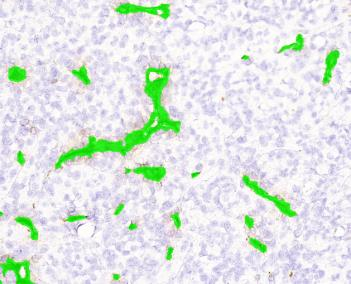

B.细胞膜定量分析 细胞膜自动检出,对于膜染色的区域,可以“一键式”完成膜检测,并进行面积、强度等的分析,快速准确,并根据软件自有算法,转换评分;

图二膜检测